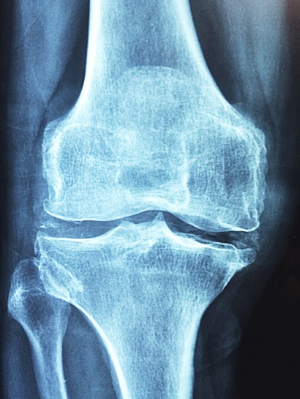

3. 관절 부음

류마티스 관절염은 주로 양쪽의 대칭적인 작은 관절을 표적으로 합니다. 손가락, 발가락의 관절, 손목, 발목, 팔꿈치, 무릎 등이 부어오르고 아프며 따끔거립니다. 이런 부음은 염증으로 인해 관절 주변의 활막이 팽창하고 관절액이 증가하기 때문입니다.